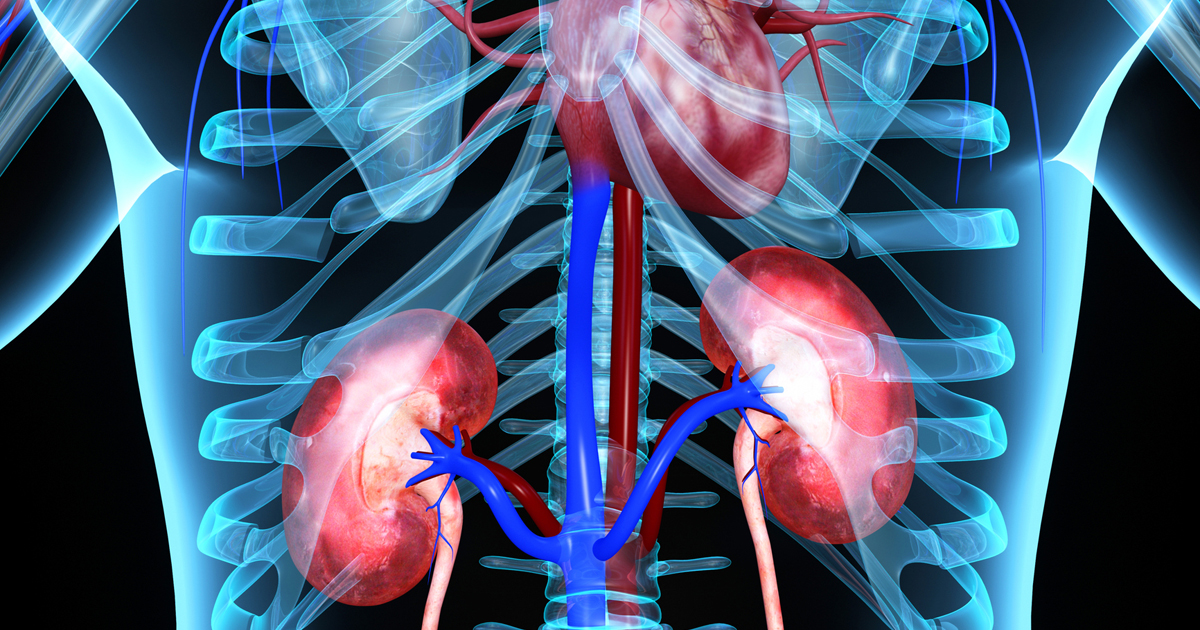

Your kidneys play a vital role in filtering blood, balancing fluids, and removing waste from your body. While most people are born with two kidneys, a single healthy kidney can perform nearly all necessary functions.

In fact, thousands of kidney donors and individuals born with one kidney lead perfectly normal lives. The remaining kidney often enlarges slightly to take over the function of both — a process known as compensatory hypertrophy.